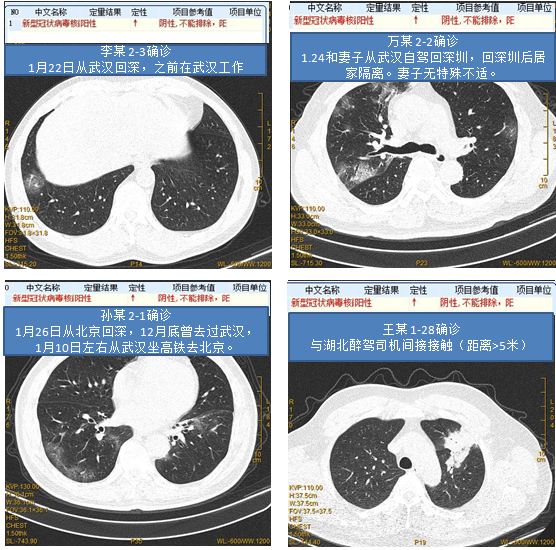

确诊新型冠状病毒感染或NCP的案例